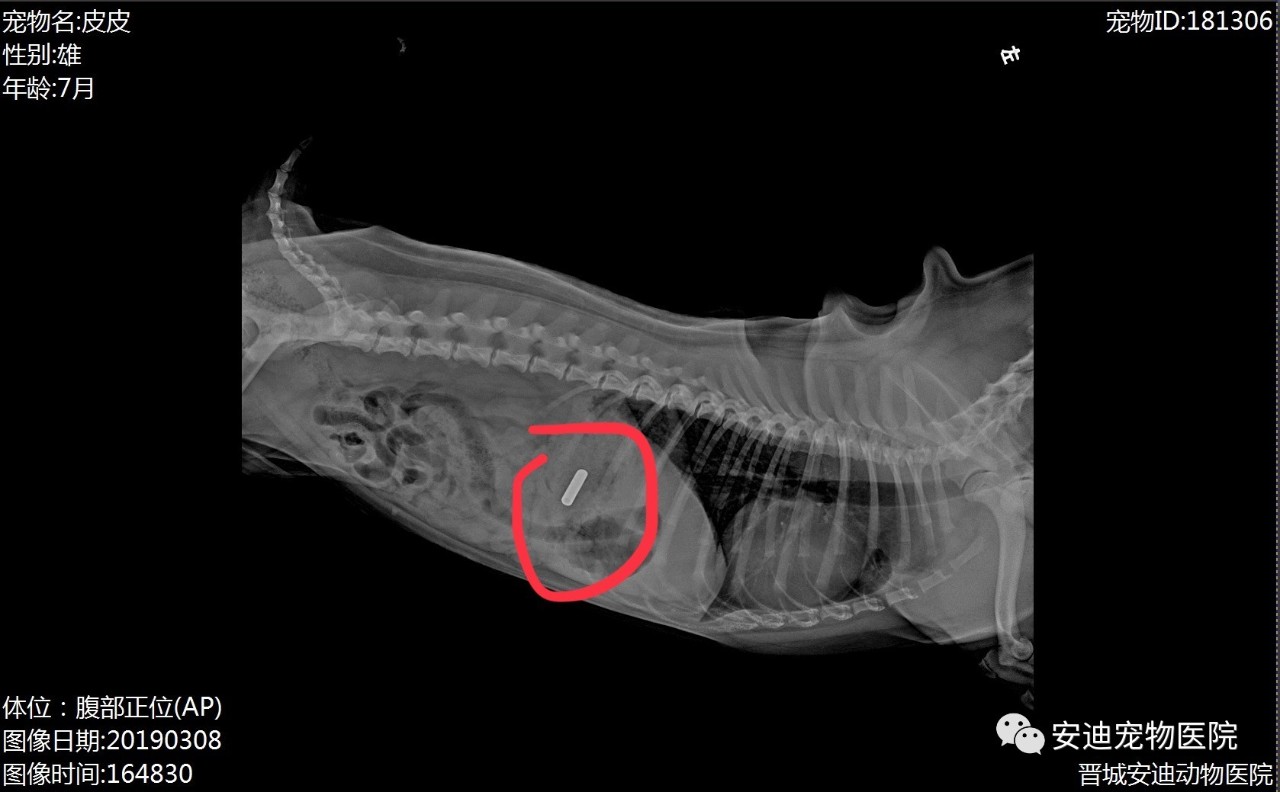

主人帶皮皮來安迪寵物醫(yī)院就診,醫(yī)務(wù)人員聽完主人的表述第一時(shí)間給皮皮拍了片子,DR顯示胃內(nèi)有可疑物品!

上圖為皮皮胃內(nèi)取出的異物,紅色標(biāo)記為DR顯示的可疑物品,傳統(tǒng)的胃異物治療方式就只有手術(shù)治療,術(shù)后恢復(fù)時(shí)間較長(zhǎng),狗狗也要忍受皮肉之苦,主人都很心疼,但是如果不做手術(shù),狗狗肯定都是性命不保!難道我們都沒有其它更好風(fēng)險(xiǎn)更低創(chuàng)傷最小或者沒有創(chuàng)傷的治療方法嗎?這個(gè)安迪寵物醫(yī)院真的有!全市唯一一家擁有寵物內(nèi)窺鏡的醫(yī)院!

黑色標(biāo)記為胃內(nèi)黏膜潰瘍部位呼吸麻醉,皮皮靜靜的躺在手術(shù)臺(tái)上,取出異物加上對(duì)胃內(nèi)黏膜進(jìn)行全面檢查,發(fā)現(xiàn)由于異物刺激皮皮的胃黏膜有幾處潰瘍,用時(shí)半小時(shí)!停了麻藥皮皮很快蘇醒,沒有任何創(chuàng)傷,從就診到皮皮離開醫(yī)院僅僅用了兩小時(shí),回去吃三天修復(fù)胃黏膜的藥,滿血復(fù)活的皮皮都不知道發(fā)生了什么!